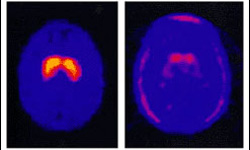

MRI scan of (left) a healthy brain, and a that of a Parkinson sufferer. Could stem cells be used to treat such degenerative disorders effectively? |

More and more of us are suffering from incurable diseases such as Parkinson's and Alzheimer's in which our nervous systems are degenerating.

Stem cells offer a lifeline for these patients, as they can be turned into replacement neurons to be transplanted into diseased brains.